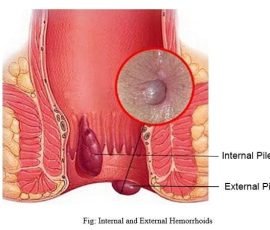

The procedure is exclusively used for the treatment of internal haemorrhoids which provides an option for patients with grade 1 or 2 haemorrhoids who may otherwise have opted for banding or sclerotherapy or for patients with more severe grade 3 or 4 haemorrhoids as an alternative to surgery.

Treatment of haemorrhoids:

Haemorrhoids without symptoms generally does not require treatment. If, however, they protrude from the anus during defecation, cause pain and/or bleeding, medical intervention may be necessary. Several treatments are available, depending on the haemeorrhoid location and severity.